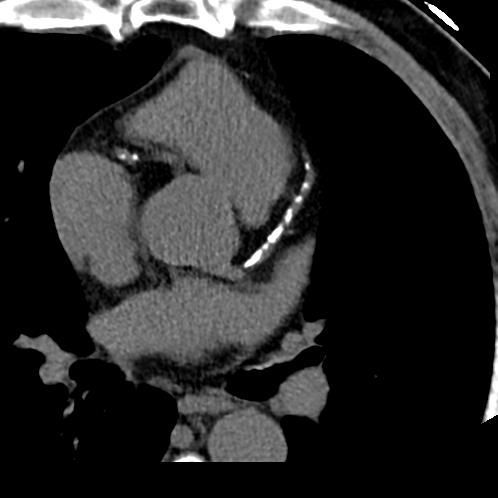

Coronary Artery Calcium Scan

Pericardium (evaluation available within full body scan)

Heart Valve Calcification (Evaluation available within Full Body Scan)

Heart Size Assessment (Evaluation available within Full Body Scan)

Your calcium score will tell us if plaque deposits are present and how severe they are. Zero is the only perfect score. The higher your score, the higher your risk of a heart attack or other cardiovascular disease. Your score also indicates how urgent it is for you to see your primary care provider for further evaluation.